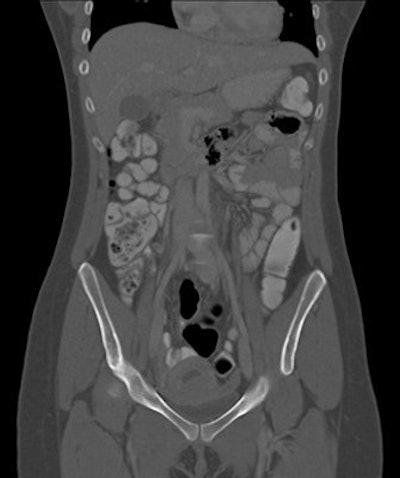

- 8 abdominopelvic CT exams

The number of CT exams of pregnant patients increased from three to four per year in 2008 to 2011 to 11 per year in 2012, a result that corresponding author Dr. Federica Zanca, also from University Hospitals Leuven, called "surprising" in an email to AuntMinnieEurope.com. In addition, three pregnancies were found by accident on abdominopelvic CT, which Zanca said was also surprising.

Abdominopelvic CT | 28.7 (range: 6.7-60.5) |

The radiation dose for all but the abdominopelvic CT exams were considered negligible, according to the researchers.